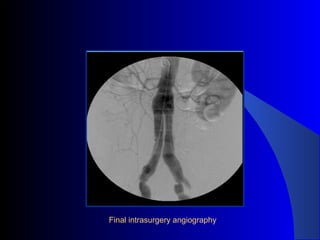

The document discusses the clinical application of the Endurant stent graft system in treating aorto-bisiliac aneurysms, detailing procedures performed on two male patients aged 72 and 73. Each patient had a history of dyslipidemia and carotid atherosclerosis, with procedures involving the bilateral bell bottom technique and the use of coils and fibrin glue. It includes pre-surgery imaging, intrasurgery angiography, and follow-up control scans to monitor outcomes.